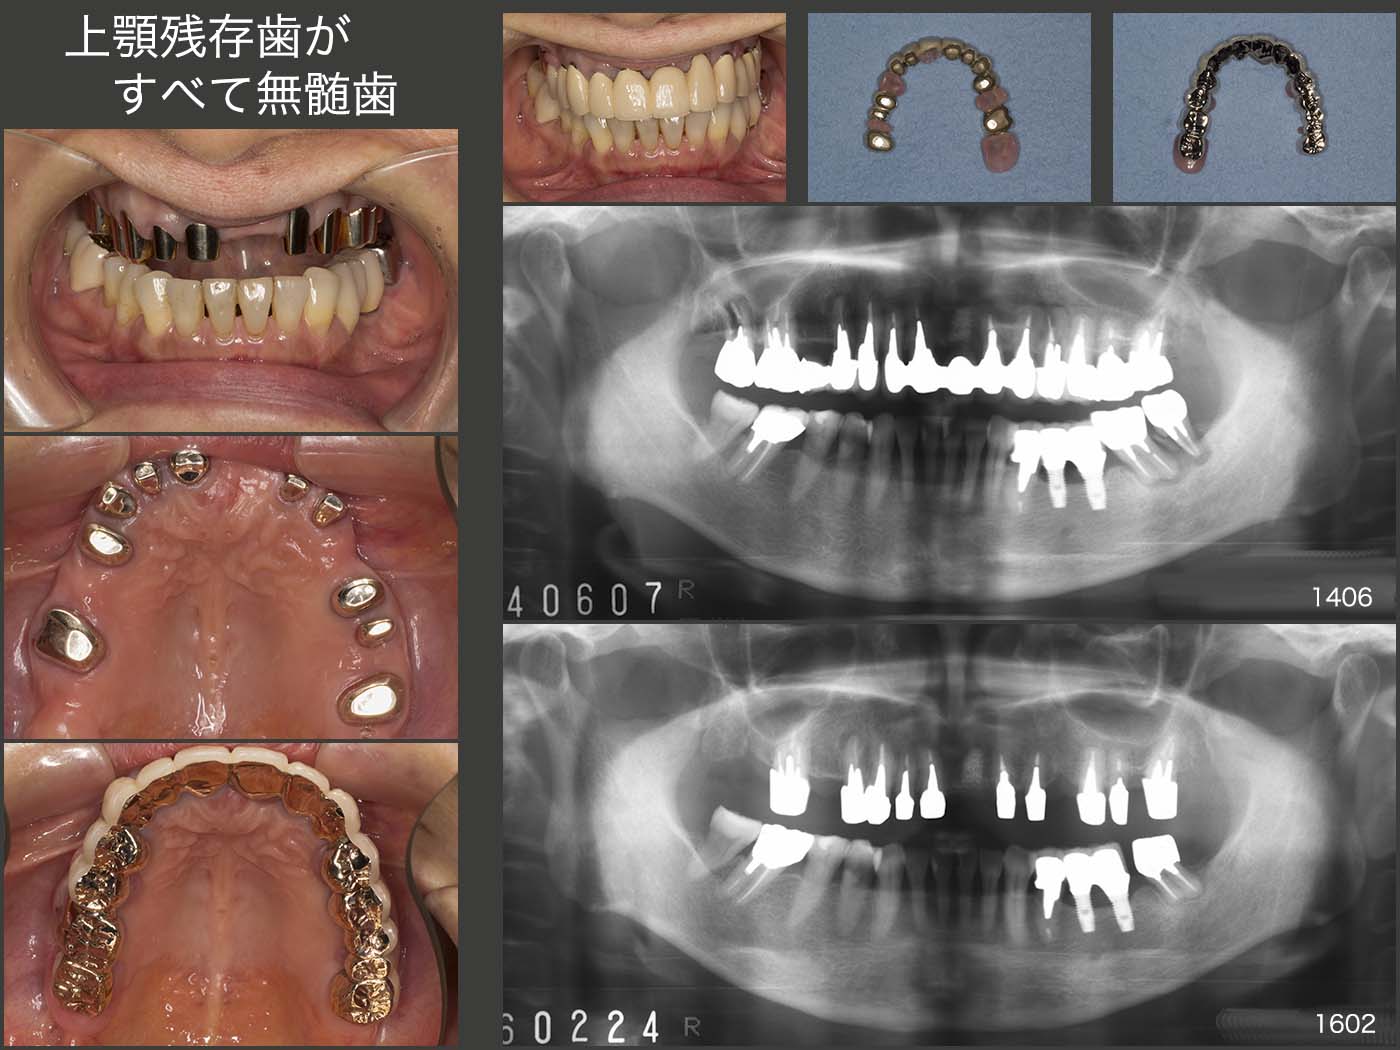

1.上顎残存歯がすべて無髄歯

2014年6月初診,65歳女性.左下8の歯根破折,破折片が舌に触れるが主訴.同部および左上4,右上7の合計3本に歯根破折が認められた.左下8および右上7は抜歯後,暫く放置しても大きな問題はないが,左上4を抜歯するとなると,設計が難しくなる.患者さんは左上4の補綴処置を希望されたので,結局上顎すべての治療にならざるを得なくなってしまった.この理由は,上顎残存歯がすべて無髄歯であり,しかもメタルコアが太く,長いために,どの歯に将来歯根破折が生じてもおかしくないからである.そこで固定式のブリッジを諦めてもらい,可撤式のコーヌス義歯を選択してもらった.

一方,インプラントを欠損部に装着する歯科医もいると思うが,隣在歯が歯根破折した場合,またインプラントを植立することになり,この先何本打つのですか?ということになりかねない.その点コーヌス義歯なら,歯が抜けたとしても義歯の外形は変わらないので,まず半永久に使用できるであろう.

20年9月現在,特に問題は生じていない.